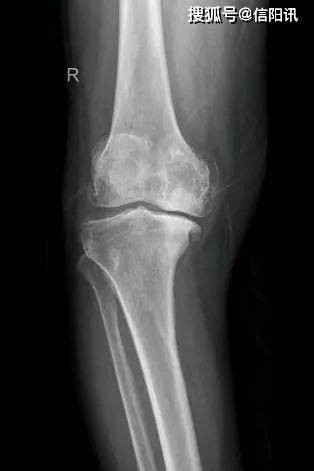

光山县人民医院骨科成功开展全膝关节置换术

青岛海慈医院王相利 你的膝关节炎适合做膝关节置换手术吗